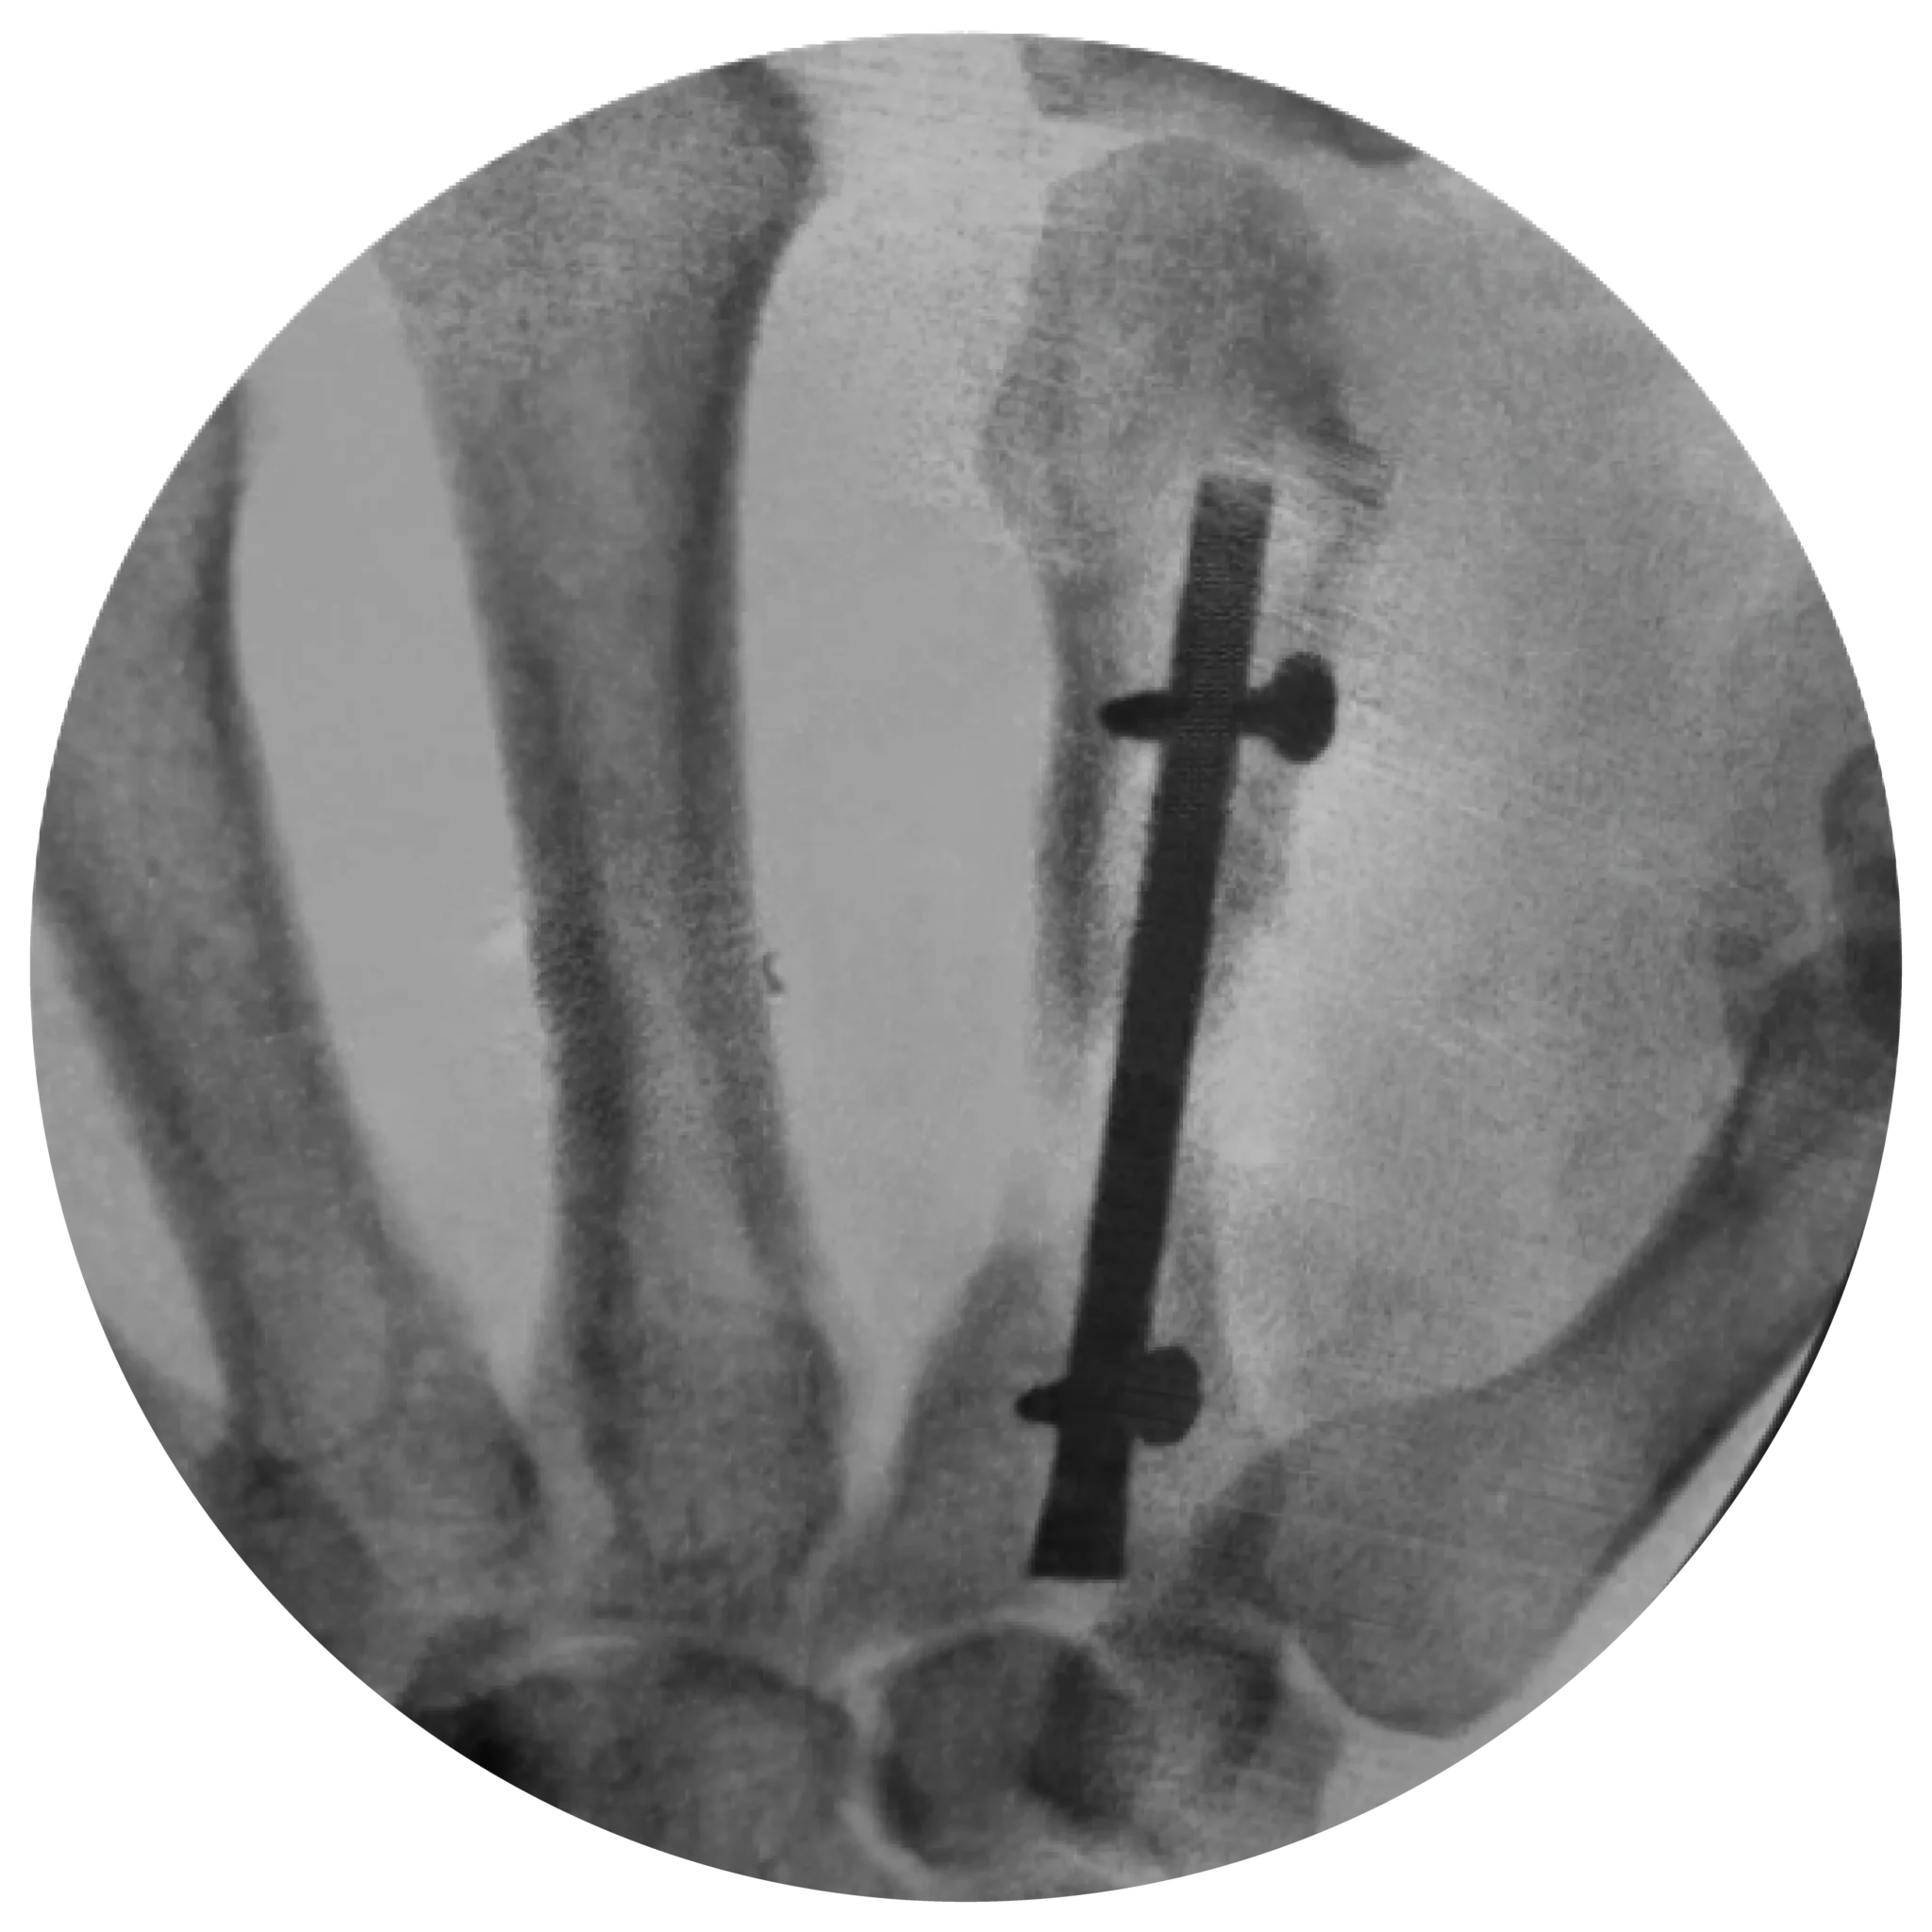

Ideal for Complex Fractures: Perfect for scenarios with bone comminution or loss, where maintaining length and preventing rotation are critical.

Enhanced Stability: Locking compression screws compress the nail to the endosteal surface.